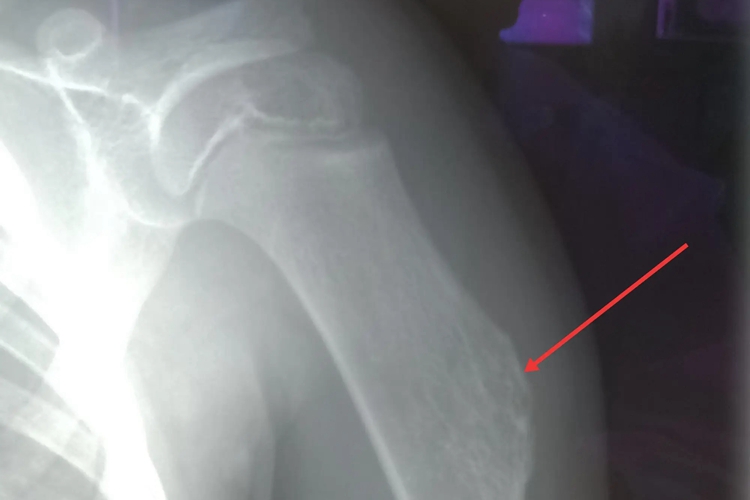

骨软骨瘤X线表现在干骺端可见从皮质突向软组织的骨性凸起,出现炎症或恶变时,需要积极治疗。

骨软骨瘤可单发或多发,X线可见在干骺端从皮质突向软组织的骨性突起,皮质连续,突起表面为软骨帽,不显影,厚薄不一,有时可呈不规则钙化影。